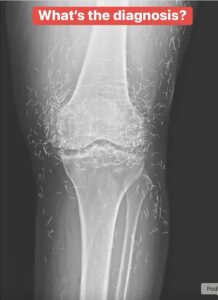

When a 65-year-old woman from South Korea sought treatment for knee pain, the doctors did not expect to find something extraordinary. However, that is exactly what they discovered.

Consequently, she sought acupuncture, as reported in a case published in the New England Journal of Medicine.

Acupuncture, an alternative treatment with a history spanning centuries, entails the insertion of needles into specific points on the body to alleviate pain or address various health issues. In this particular instance, the needles—likely crafted from gold—were deliberately left in her knees to provide ongoing stimulation.

He further cautioned that needles left embedded can interfere with X-ray interpretations. “The needles may obscure certain anatomical structures,” Guermazi remarked in 2013.